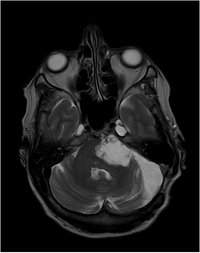

Epidermoid - T1 mit KM - axial

Keine Kontrastmittelaufnahme

DD: Arachnoidalzyste, mit  Liquorsignal in allen Sequenzen